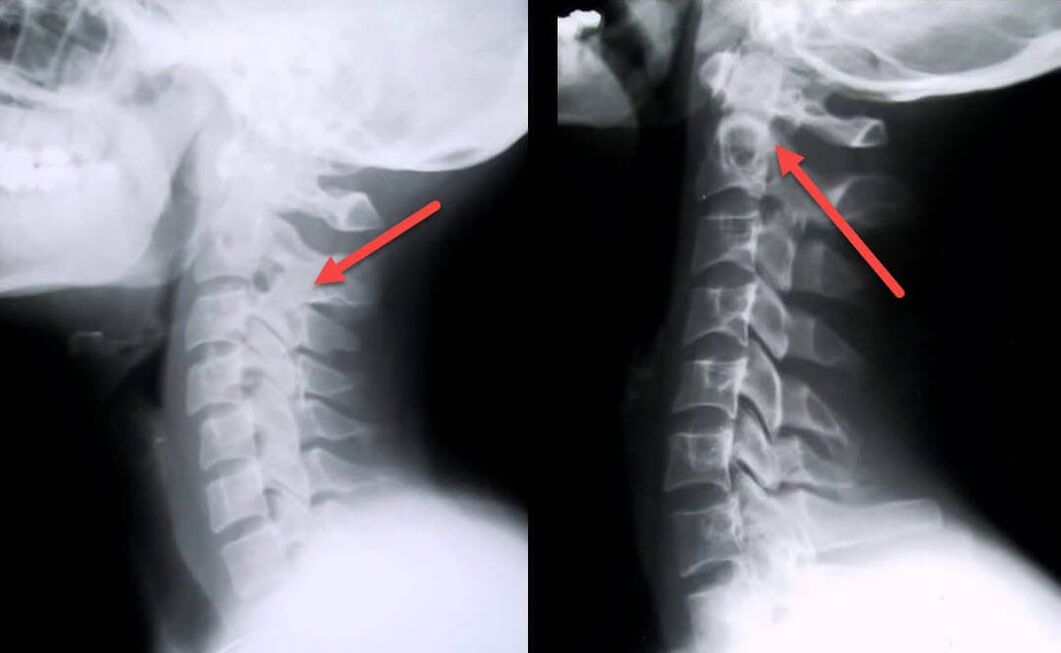

The most informative diagnostic procedure is radiography.Grade 1 pathologies correspond to radiological stage 1 or 2.The resulting images display the typical symptoms of the disease.

| X-ray stages of cervical osteochondrosis of the 1st degree | Characteristic signs |

|---|---|

| Stage 1 | Small changes in the curvature of the spine in the cervical region affect one or more segments |

| Stage 2 | Slight thickening of intervertebral discs, deformation of marginal processes, correction of lordosis, small growths of bone structures |